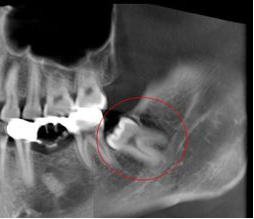

所以拔智齿会损伤神经吗

看下图

如果是处于特殊位置的智齿,还是有可能的

(但概率极低)